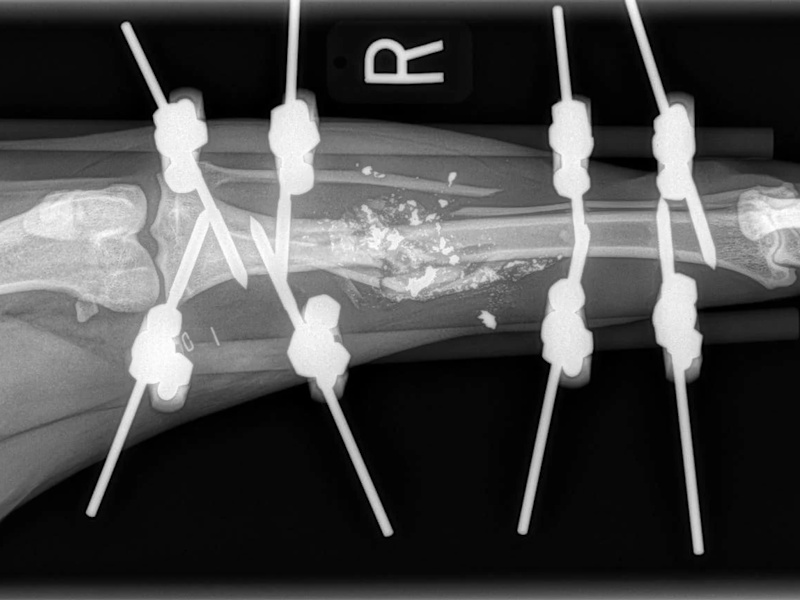

Carpal Hyperextension

- Pan-Carpal Arthrodesis: $6,500 - $8,000+

- Partial Carpal Arthrodesis: $5,250+